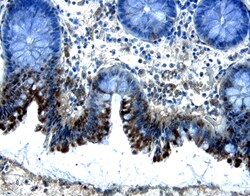

Invitrogen™ SMAD5 Polyclonal Antibody

Brand: Invitrogen™ PA5148580

| Immunohistochemistry (Paraffin), Western Blot | |

| E. coli-derived recombinant human Smad5, Val155-Arg258. | |